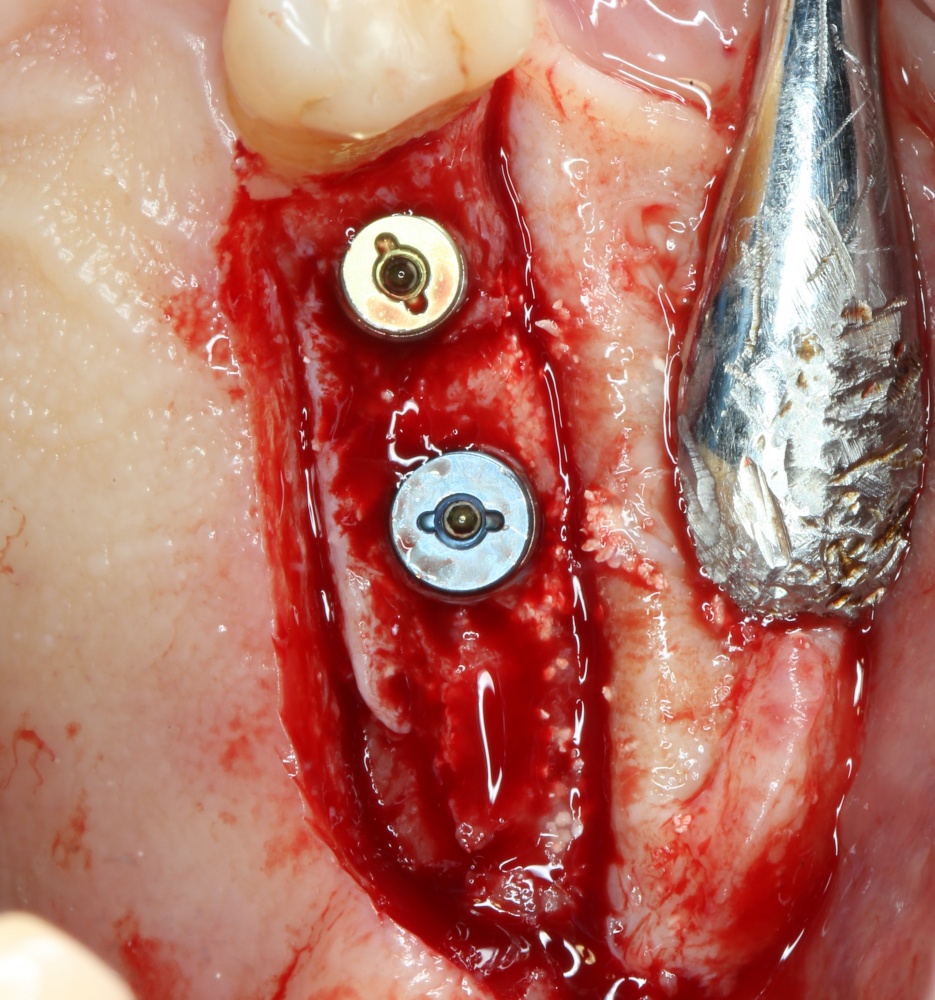

Я зафиксировал костный блок практически без адаптации на несколько винтов. Обрати внимание, что винты находятся в зоне, где не планируется установка имплантатов. Фиксация должна быть надежной, поскольку мне еще предстояла подготовка лунок для имплантатов. Трех винтов для этого вполне достаточно.

Дальнейшая адаптация костного блока свелась к сглаживанию острых краев. После чего я приступил к подготовке лунок и установке имплантатов.

Установка имплантатов.

Напомню, что для этой работы я выбрал субкрестальные имплантаты Ankylos C/X. Они прекрасно сочетаются с любым методом остеопластики.

Я не планирую установку супраструктур или коронок, поэтому на уровень первичной стабильности можно положить болт. Даже наоборот — чем меньше крутящий момент при установке, тем лучше. Для имплантатов Ankylos и подобных им, это особенно важно. В общем, момент силы при установке — не более 10-15 Нсм.

Ремарка: имплантаты с предустановленными имплантодержателями хороши тем, что с ними легко контролировать позиционирование имплантатов. В случае с Ankylos С/Х - еще и крутящий момент. Имплантодержатель должен отсоединяться от имплантата с легким щелчком. Если его клинит, и тебе приходится прикладывать для этого усилия, то ты, однозначно, превысил момент силы во время установки имплантата. Следовательно, жди проблем.

Глянем на то, что получилось:

Осталось адаптировать костный блок (убрать острые края), проверить его фиксацию и, при необходимости, добавить винты. Десятисекундное дело.